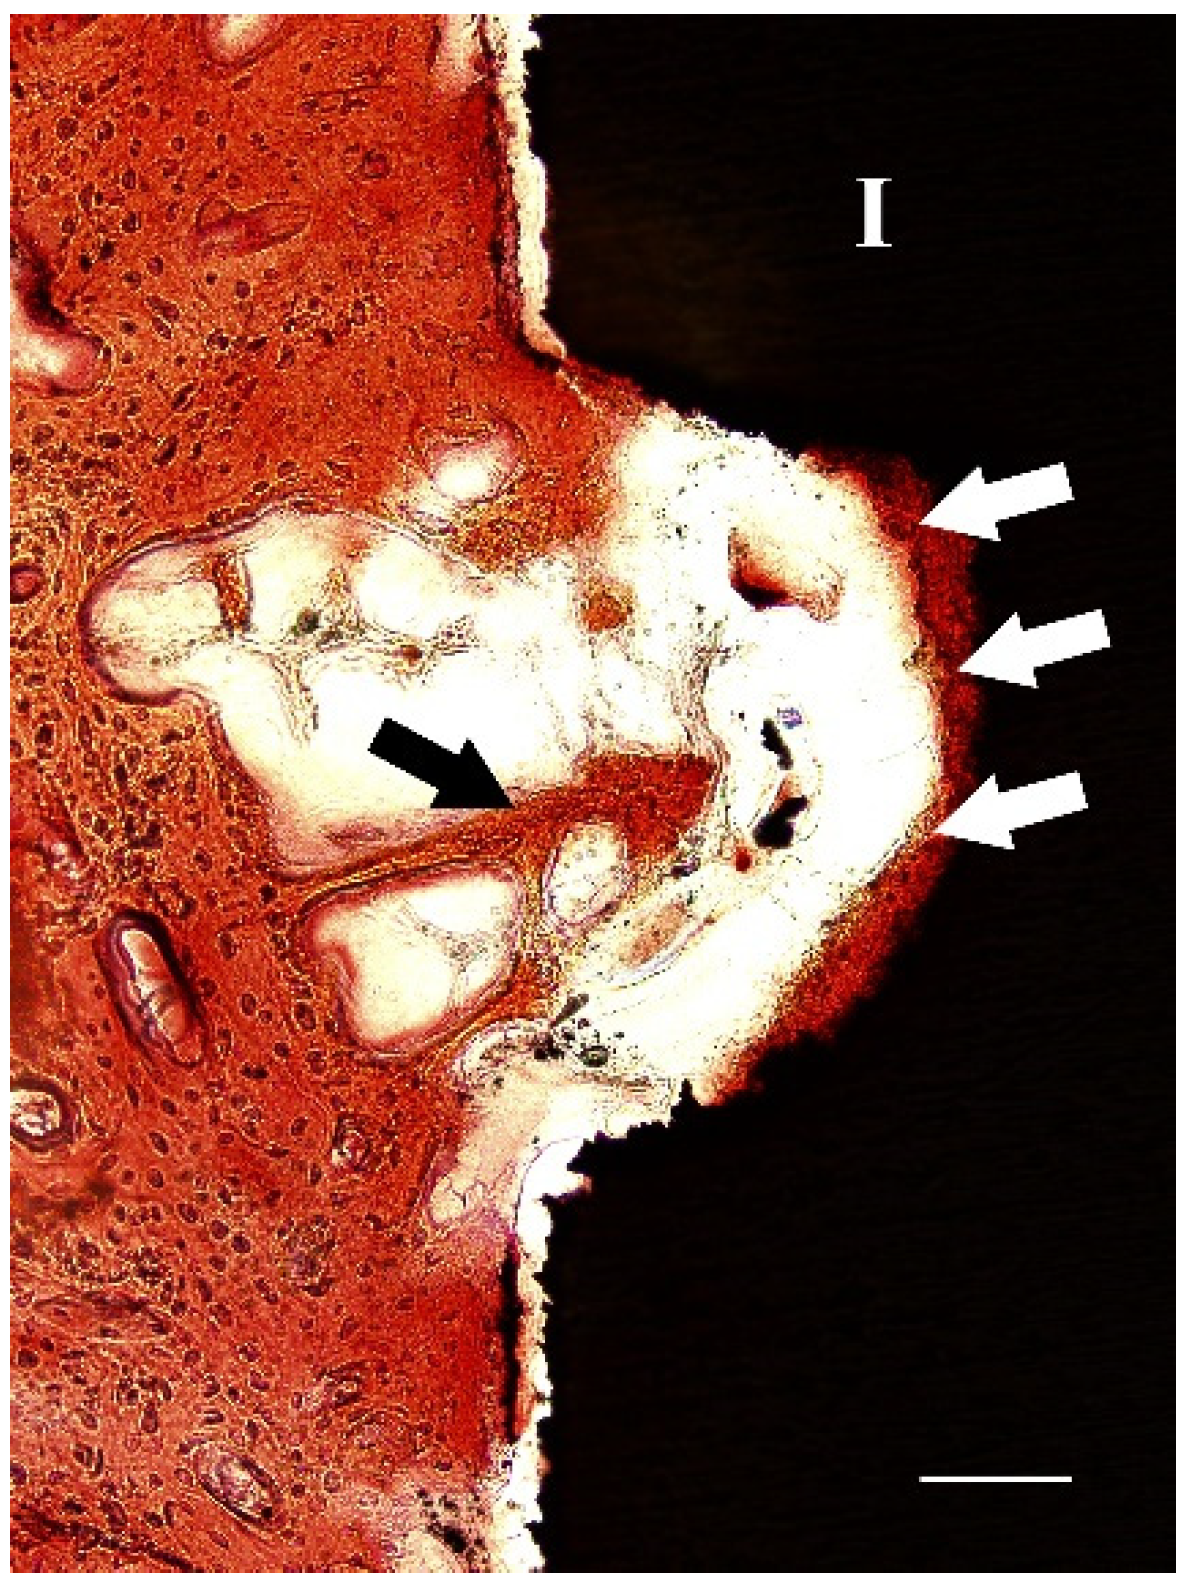

2.3. Histological Study